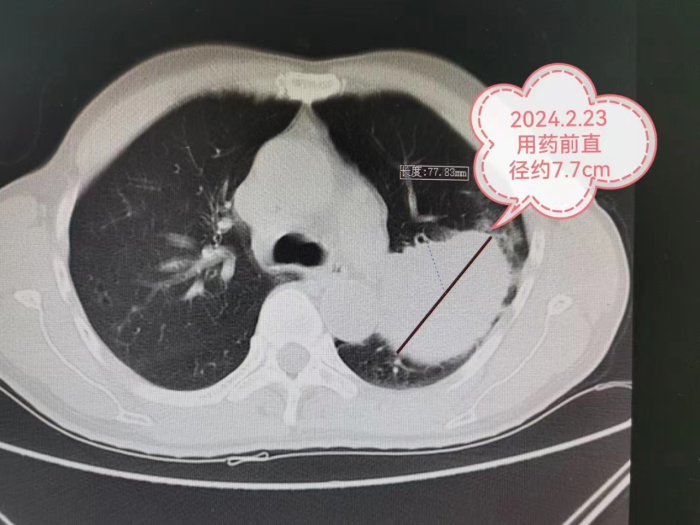

今年2月严先生因“ 反复咳嗽、咳痰3年,病情加重伴气促2月”到贵州航天医院就诊,经胸部CT检查发现左肺上叶占位,肺穿刺病理确诊为左上肺鳞癌,肿瘤大小约为66mm×77mm,且肿瘤包裹左上肺重要血管。

经过4个周期的新辅助化疗联合免疫抑制治疗后,肿瘤最大直径由77mm明显缩小到40mm,分期由IIIA期降为IIA期。

新出现的基因靶向治疗和免疫治疗特点:副作用小,患者才可以长期使用;药物有效率高,使用以后肿瘤就容易变小甚至消失。所以,基因靶向治疗和免疫治疗以更高效的速率杀灭肿瘤细胞,原本一个非常广泛发展的肿瘤,可以被安全地缩小到一定程度范围,而且还不会伤及身体的根本。手术不再是晚期患者不可企及的奢望,而是顺其自然地照进了现实。比如本文中的IIIA期肺癌患者,且肿瘤包裹左上肺重要血管,几乎没有手术机会,或者被迫切除左全肺,术后生活质量差。在免疫药+化疗药的协同作用下,肿瘤直径缩小48%,分期由IIIA期降为IIA期,于是手术机会来了,而且只切除了左上肺,保留住了左下肺,术后生活质量相对切除左全肺更好。手术切除后肿瘤残余比例不足10%,实现了主要病理缓解(MPR)。